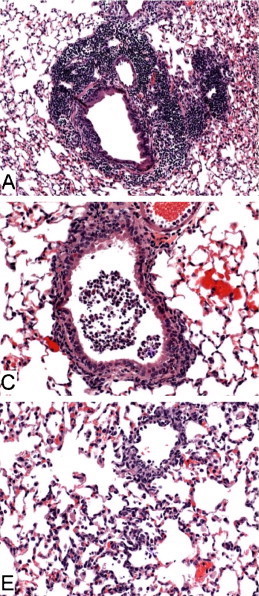

Figure Legend: Histopathology of lungs from aged 129S6 (A), B6 (C) and BALB/c (E) mice infected with SARS-CoV at 3 days post-infection. H&E stain. Adapted from Roberts, et al.5

Aged 129S6

Aged 129S6/SvEvTac mice have also been used in SARS studies, with weight loss and similar histopathological findings post-infection as in aged BALB/c and B6 mice8. According to Roberts, et al., when comparing experiments in young animals, "129S6 mice seem to be slightly more susceptible to disease associated with SARS-CoV infection than are BALB/c or B6 mice, as evidenced by an approximate 8% loss of body weight, with a nadir at days 5-7 [post-infection], and by the presence of mild interstitial pneumonitis at day 2 [post-infection]"8.